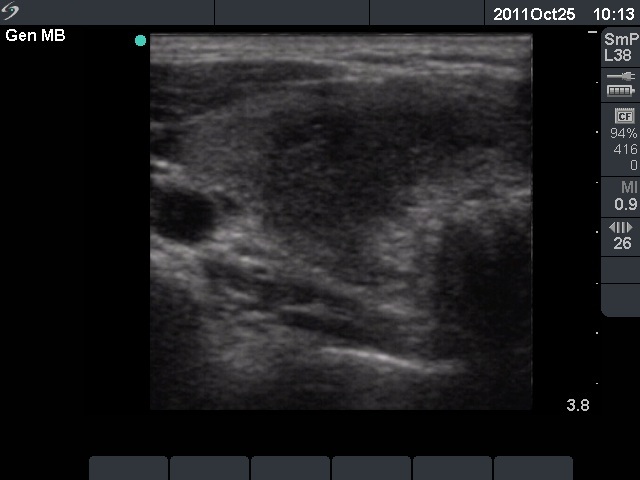

Initial examination (first row of images):

Clinical presentation: A 29-year-old woman requested a second opinion. She was in the 11th week of her pregnancy. She had mild neck discomfort for 2 months. A suspicious nodule was found in the left lobe on the evaluation. Aspiration cytology was repeatedly non-diagnostic. She was told that she had thyroid carcinoma with great probability. Her endocrinologist recommended to abort the child and then to undergo thyroidectomy.

Palpation: The left thyroid was hard on palpation, but not painful.

Ultrasonography: The right thyroid was echonormal and contained several small, insignificant lesions. There was a hypoechogenic lesion with blurred borders in the central and in the ventro-medial part of the left thyroid with increased intranodular blood flow.